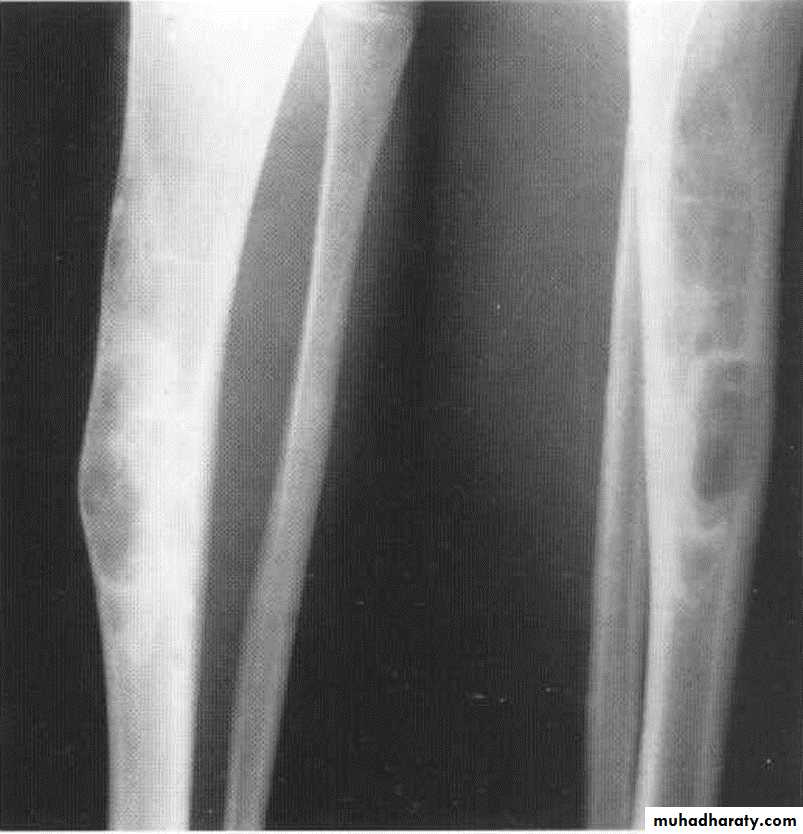

Fibrous Cortical Defect & Non ossifing Fibroma (NOF):Common incidental findings in children.

Site: affect diaphysis of long bone.

Findings: well defined lucent areas in cortex with sclerosed margin .

Osteoid osteoma:

Age: young adults

Site: tibia, femur

Findings: lucent area surrounded by calcification

nidus surrounded by sclerotic rim with or without periosteal reaction.

Radionuclide bone scan : area of increased uptake